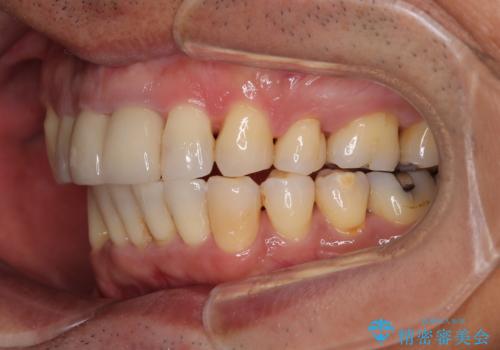

上顎前歯に装着されていた保険診療の前歯は見た目が気になるとのことであったので、矯正治療後にオールセラミッククラウンにて補綴治療を行うこととしました。

食いしばりにより奥歯がすり減っており、咬み合わせが定まるまで時間がかかりましたが、整った口もに仕上がりました。